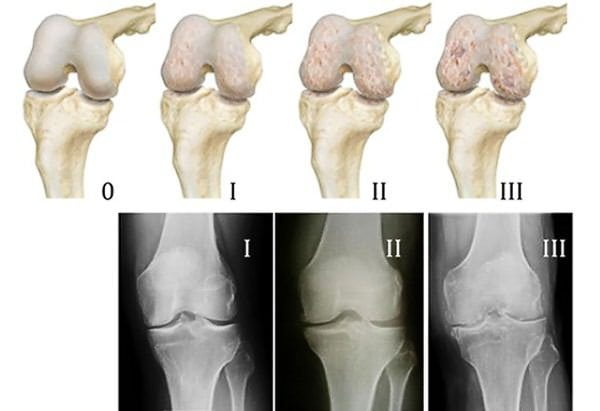

- Рентгеновское исследование. На снимке можно увидеть незначительное утолщение хрящевой ткани и слабое сужение суставной щели. Одним из ранних признаков артроза суставов 1 степени являются остеофиты – костные наросты, формирующиеся вследствие патологических изменений хряща;

Изменяется состав синовиальной жидкости, хрящ получает из нее меньше питательных веществ. Процесс разрушения хрящевой ткани усугубляется, образуется еще больше продуктов распада, формируется порочный круг, болезнь прогрессирует. Истончение, пересыхание, постепенное разрушение суставного хряща происходит при остеоартрозе 1 степени. Уже на этой стадии начинаются изменения костной ткани, которая расположена под хрящом: она уплотняется (остеосклероз), утрачивает естественный рельеф, суставные площадки приближаются друг к другу, по их краям формируются костяные наросты – остеофиты.

Артроз 2 степени характеризуется дальнейшим разрушением хряща, остеосклероз и остеофитоз становятся более выраженными, сильнее сужается суставная щель между поверхностями костей. Воспалительный процесс внутри суставной полости приводит к синовиту. На 3 стадии хрящ разрушен, суставная щель практически полностью закрыта, разрастания остеофитов приводят к выраженной деформации сустава, которой деформирующий остеоартроз обязан своим названием. В дальнейшем возможно формирование ложного сустава (неоартроз) или полное обездвиживание сустава (анкилоз). Иногда эти состояния рассматривают как 4 стадию артроза, но правильнее классифицировать их как самостоятельные заболевания.

Рентгенологические критерии

По классификации Келлгрена-Лоуренса в соответствии с рентгенологическими критериями выделяется 5 стадий артроза, от 0 до 4. На нулевой изменения отсутствуют, 1–2 стадия соответствуют клиническим проявлениям артроза 1 степени. На 1 стадии рентгенологические признаки сомнительные, на 2 выявляются минимальные изменения, а именно:

- незначительное сужение суставной щели;

- единичные мелкие остеофиты (зачатки остеофитов в виде точечных заострений или краевые наросты размерами до 1–2 мм).

По методике Ларсена можно оценить количественные изменения в суставе. К 1 стадии, согласно этой классификации, относится сужение суставной щели менее чем на 50%. (Измерения проводятся на наиболее суженном участке, который подвергается максимальным механическим нагрузкам).

Уже на ранней стадии артроза могут отмечаться слабовыраженный субхондральный остеосклероз (уплотнение подхрящевой костной ткани) и околосуставный краевой дефект костной ткани (эрозия). Еще одна классификация стадий артроза предложена Косинской. Согласно этой классификации, на 1 (начальной) стадии патологический процесс ограничивается хрящом и не затрагивает костную ткань, синовиальную оболочку, связки и мышцы. К рентгенологическим критериям 1 стадии Косинская относит только незначительное сужение суставной щели, которое можно выявить, сравнивая снимки симметричных суставов.